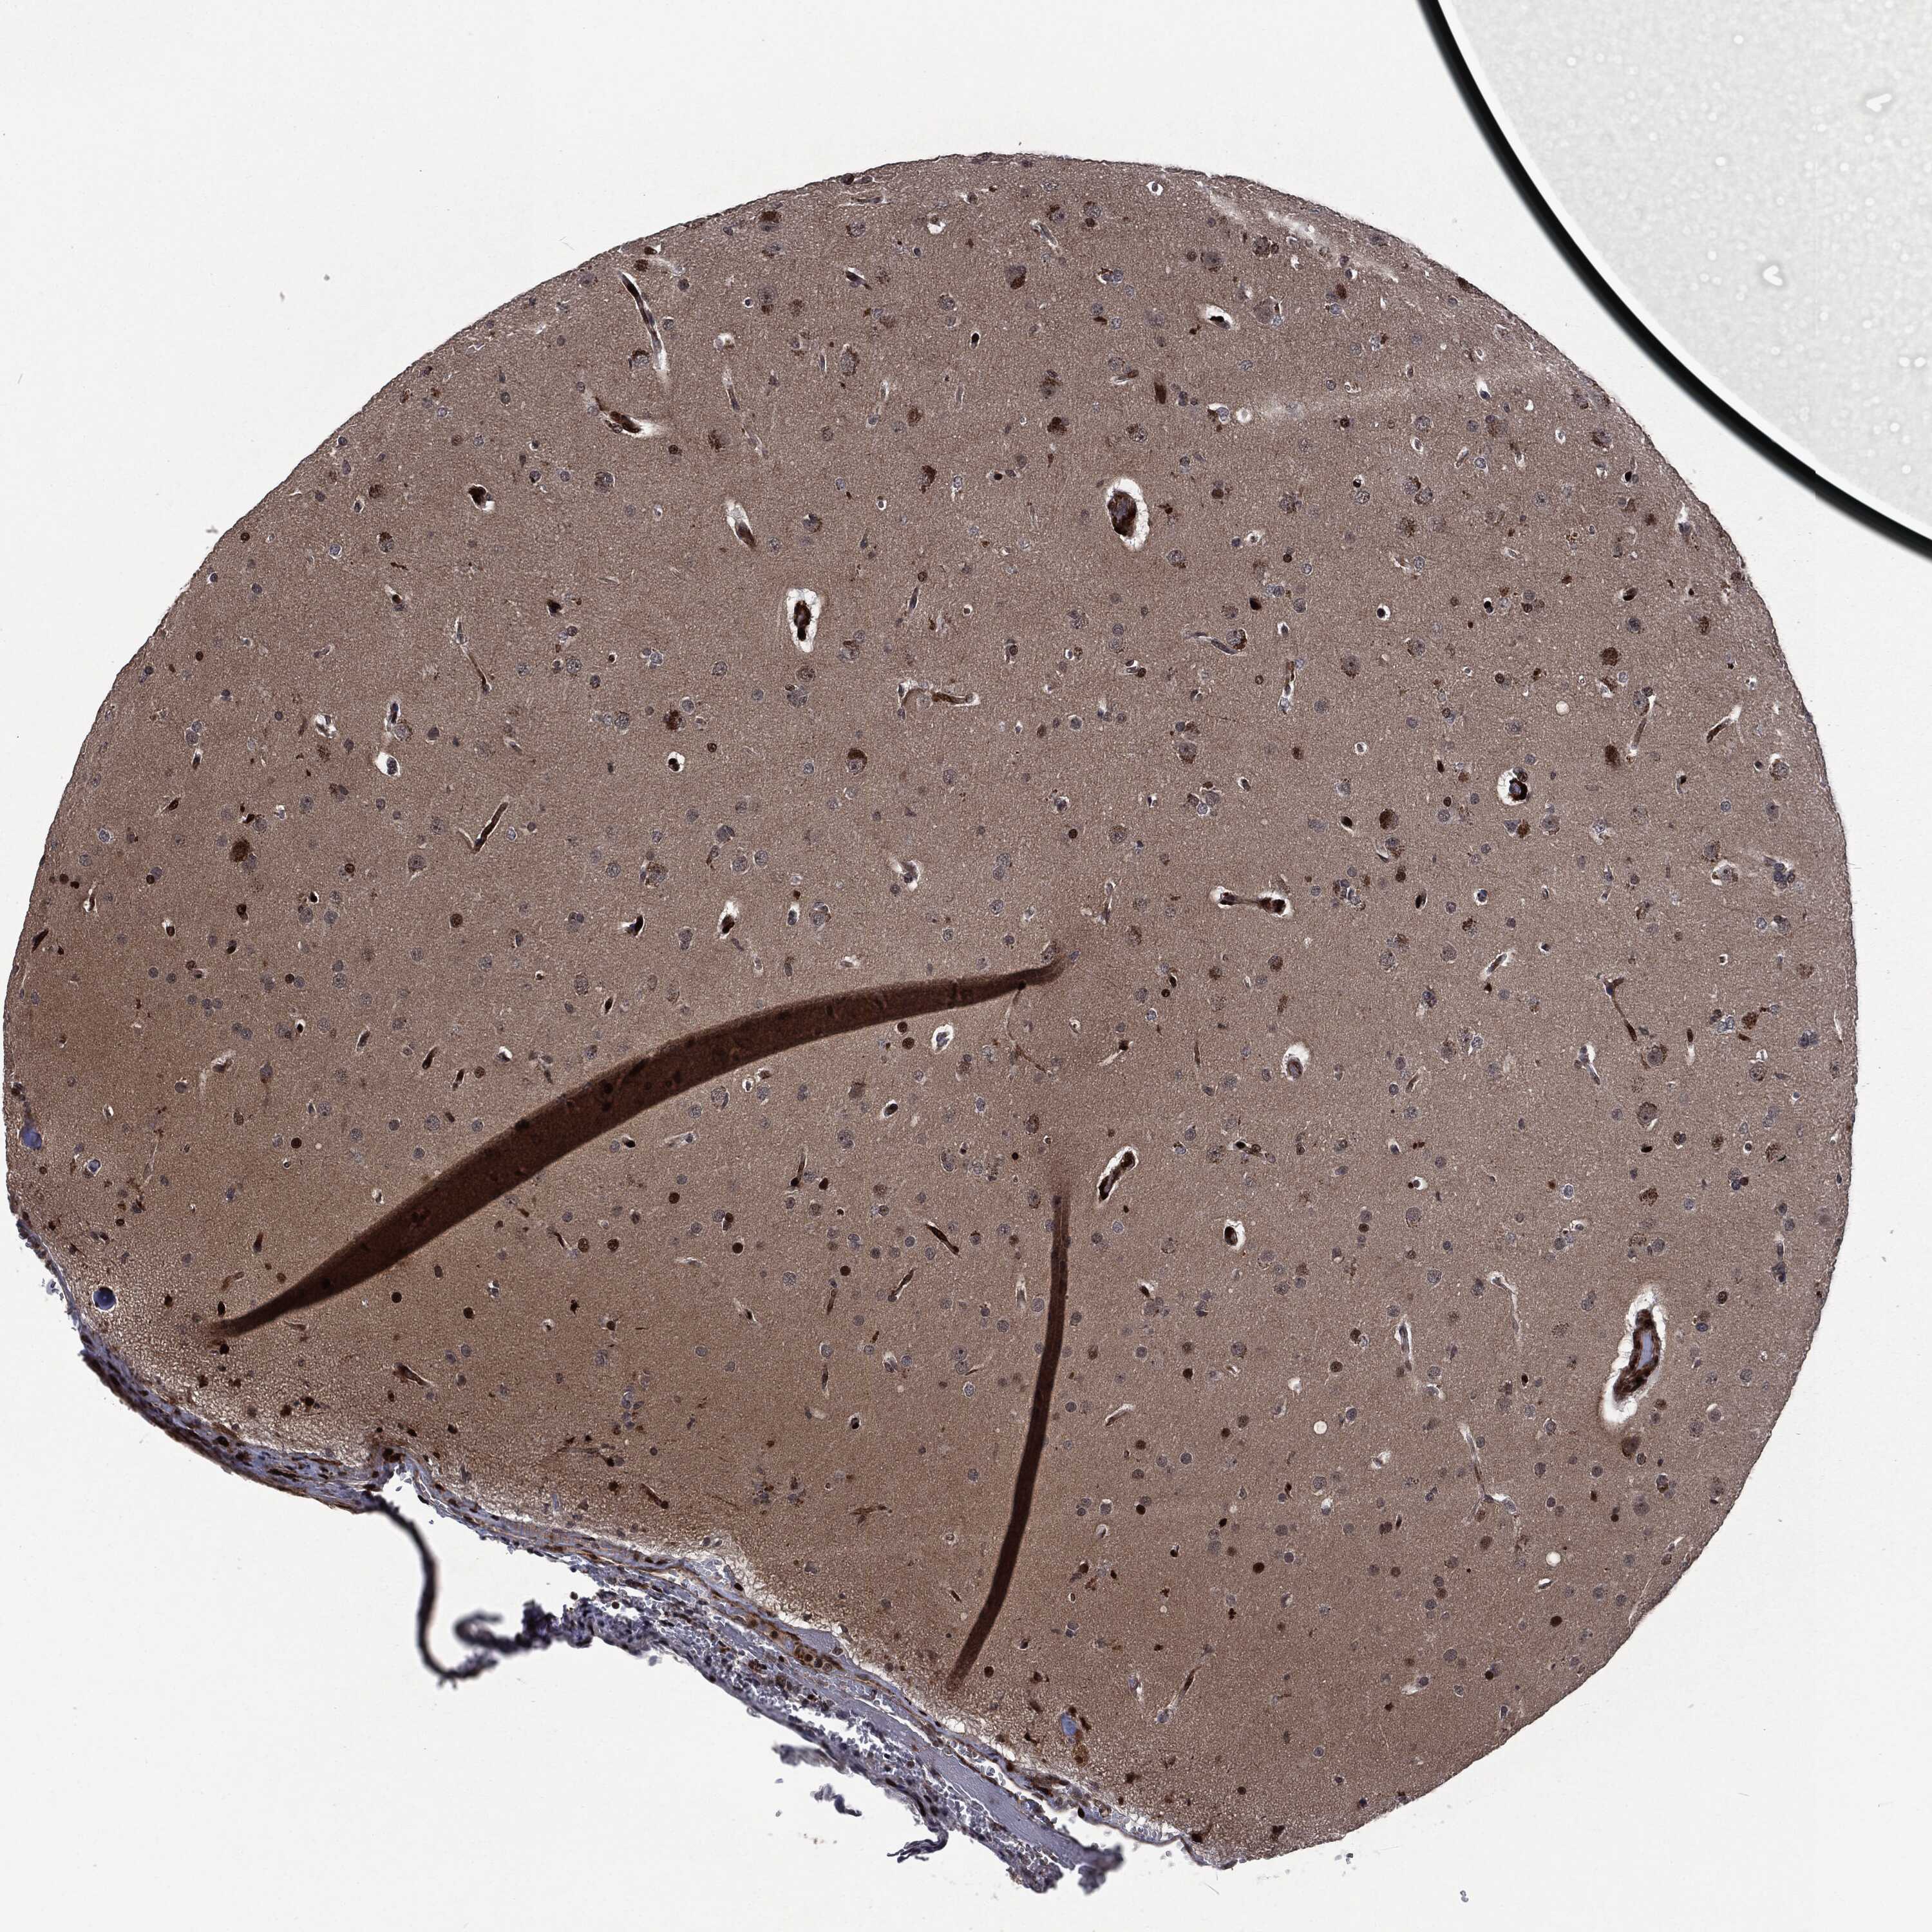

GLIOMA - Protein expressioni

A mouse-over function shows sample information and annotation data. Click on an image to view it in a full screen mode. Samples can be filtered based on level of antibody staining by selecting one or several of the following categories: high, medium, low and not detected. The assay and annotation is described here.

Note that samples used for immunohistochemistry by the Human Protein Atlas do not correspond to samples in the TCGA dataset.

Antibody stainingi

Antibody staining in the annotated cell types in the current human tissue is reported as not detected, low, medium, or high, based on conventional immunohistochemistry profiling in selected tissues. This score is based on the combination of the staining intensity and fraction of stained cells.

Each image is clickable and will lead to virtual microscopy that enables deeper exploration of all samples and also displays staining intensity scores, fraction scores and subcellular localization as well as patient and tissue information for each sample.

Glioma, malignant, High grade

Glioma, malignant, Low grade

Glioma, malignant, NOS